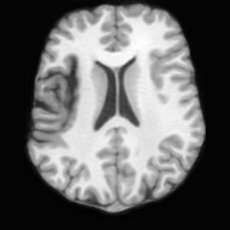

PathologicalSynthSR [18]Brain-ID [28]UNA [30]USBRefer to captionRefer to captionRefer to captionRefer to captionRefer to captionRefer to captionRefer to captionRefer to captionRefer to captionRefer to caption

Figure D.1: Comparison of pathology-to-healthy editing results on real stroke brain images from the ATLAS dataset [27].

Editing as Healthy Reconstruction for Patient Scans. Fig. D.1 illustrates the results of different methods applied to real stroke pathological brain images from the ATLAS dataset [27]. As shown, for relatively small lesions (first row), competing methods can partially reconstruct healthy brain structures, yet the results are noticeably inferior to those produced by USB. For larger lesions (second row), all other methods fail to recover the healthy regions, whereas USB successfully restores anatomically plausible healthy brain structures. These observations demonstrate USB’s superior ability to handle a wide range of lesion sizes and its robustness in generating anatomically plausible healthy reconstructions from real pathological scans, even though the model was trained solely on pseudo-synthetic pathological data.